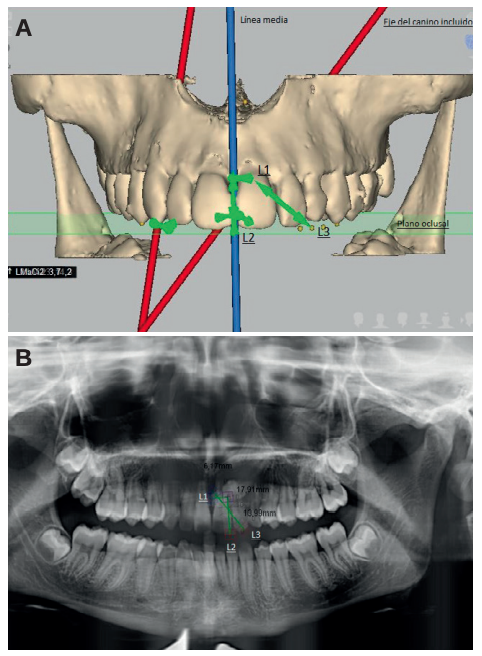

Methods: An orthodontic study of the maxilla using orthopantomography with cone beam computed tomography (CBCT) at the Madrid European University Clinic was performed on 27 patients selected with 36 maxillary impacted canines. Three reference lines were drawn based on the distance from the cusp of the canine to the occlusal plane (L1), to the midline (L2) and to its ideal eruption site (L3), in both the orthopanthomography and the CBCT. As ideal reference values, we selected a control group of 36 erupted maxillary canines.

Results: The results were compared in 2 and 3 dimensions using the Student’s t test, after verifying their normal distribution using the Anderson-Darling contrast test. Statistical significance (p > 0.05) was not obtained for any of the variables studied.